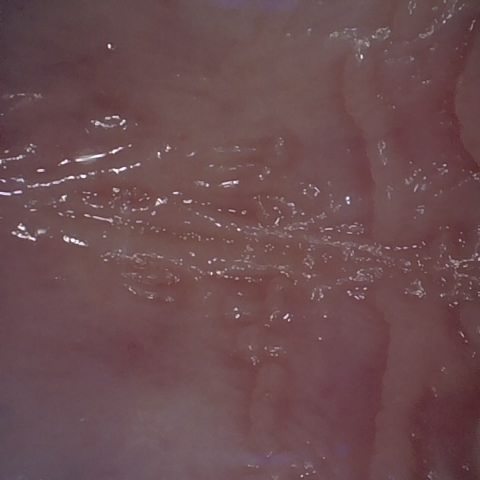

Annotated as "Good"